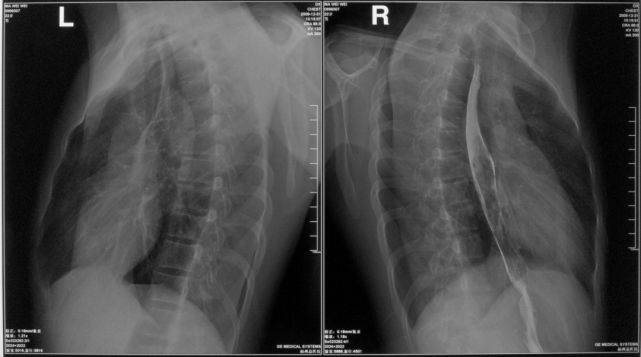

左下叶支气管扩张

图片

左下叶支气管囊状、柱状扩张

右肺支气管扩张

右肺支气管呈囊状、柱状扩张